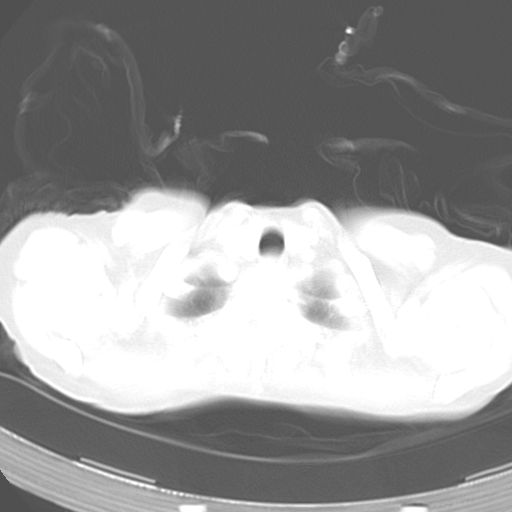

以下是引用dyqct在2006-12-7 21:08:00的发言:[br]考虑:1、肝内外胆管多发性结石伴肝左叶外侧段肝萎缩;[br] 2、右膈下多发脓肿;[br] 3、右侧少量胸腔积液、斜裂积液;[br] 4、左肾囊肿。

以下是引用jiazh在2006-12-7 20:37:00的发言:[br]肝脏周围半狐形低密度影,肝脏表面受压推移,考虑膈下脓肿可能性大;2、右侧胸腔积液

以下是引用拾荒者在2006-12-7 21:44:00的发言:[br]肝内外胆管多发结石,右膈下多发脓肿,右胸膜腔及叶间裂积液,左肾囊肿。[br] [br]